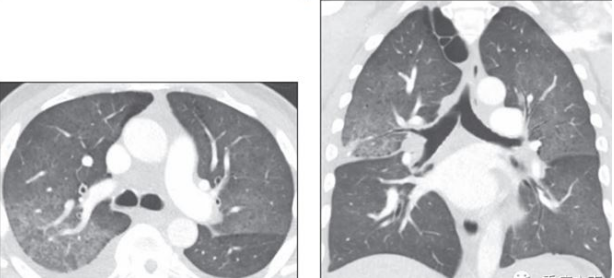

胸部CT

胸部CT可见双肺大片渗出实变影(图1)

图1  患者胸部CT(2020-10-09)